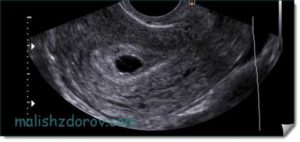

Данный вид исследования в кругу врачей считается более точным. Обычно именно он назначается для изучения состояния органов малого таза. Возможным считается также его применение при беременности на ранних сроках.

По результатам вагинального УЗИ можно выяснить стадию развития плода, рассмотреть самые незначительные аномалии и выяснить причину повышенного тонуса живота. Насколько необходимо проведение этой процедуры на маленьком сроке, решает непосредственно врач. Обычно это связано с какими-то патологиями, заболеваниями матери или проявлении негативных симптомов (кровотечение, боли внизу живота).

Таким методом допускается проводить изучение состояния плода на сроке до 12 недель. При этом в совокупности с анализами (мазками) он даст более точную картину. Однако большинством женщин процедура признается довольно неприятной, поэтому без указания на то гинеколога, ее обычно не проводят.

Трансвагинальный датчик используют в первом триместре только в случае сомнительных результатов обычного УЗИ. Такой вариант помогает лучше просматривать матку и придатки из-за близости к этим органам. При процедуре во влагалище вводят тонкий прибор, на который надевают презерватив.